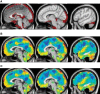

The discovery that spontaneous fluctuations in blood oxygen level-dependent (BOLD) signals contain information about the functional organization of the brain has caused a paradigm shift in neuroimaging. It is now well established that intrinsic brain activity is organized into spatially segregated resting-state networks (RSNs). Less is known regarding how spatially segregated networks are integrated by the propagation of intrinsic activity over time. To explore this question, we examined the latency structure of spontaneous fluctuations in the fMRI BOLD signal. Our data reveal that intrinsic activity propagates through and across networks on a timescale of ∼1 s. Variations in the latency structure of this activity resulting from sensory state manipulation (eyes open vs VSports手机版. closed), antecedent motor task (button press) performance, and time of day (morning vs. evening) suggest that BOLD signal lags reflect neuronal processes rather than hemodynamic delay. Our results emphasize the importance of the temporal structure of the brain's spontaneous activity. .